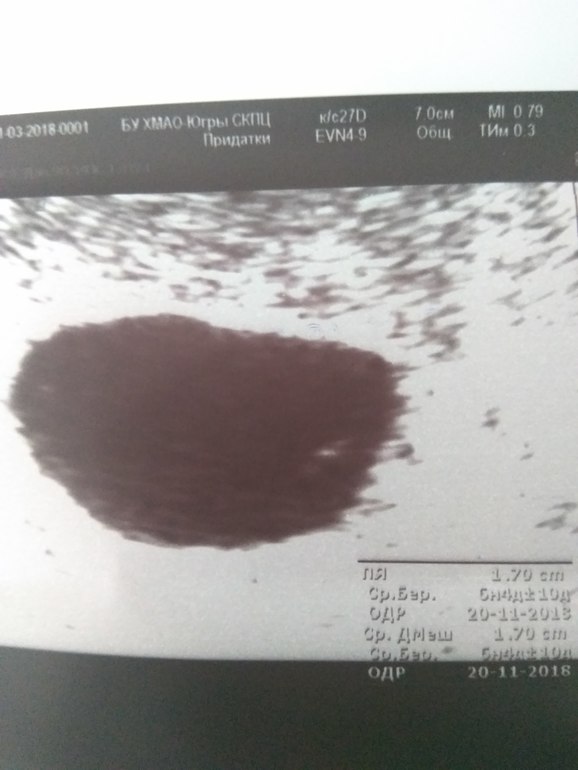

Сегодня была на УЗИ. Акушерский срок 7 недель. ХГЧ 30.03 - 10395.

тут хгч даже уже не соответствует сроку, у меня на 7 неделях было уже 72 тыс. про размеры молчу.

В 7 недель хотя бы должно быть видно желточный мешок...

Я не врач, но... почему не сделать ещё контрольное УЗИ через неделю? Может, он ещё крохотный совсем? Пя ещё не больше 20мм, если не ошибаюсь, то до определённого размера пя мониторят... а желточный мешочек растёт?

Это и есть анэмбриония... Но я схожу ещё в понедельник на УЗИ. Мало ли...